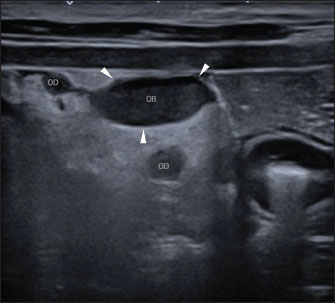

A Canon Aplio i600 ultrasound machine with convex (9-10.8 MHz) and linear (12-18 MHz) probes was used. The conscious patient was positioned in both the lateral and dorsal recumbencies. Moderate distension of both uterine horns (up to 17 mm in diameter) with immobile hyperechoic intraluminal content and irregular walls with multiple mural ovoid anechoic lesions were noted (Fig. 2). Cranial to the ovarian end of the right uterine horn and surrounding the right ovary, a 25-mm, well-defined, irregular lesion filled with mildly echogenic fluid was observed, which was compatible with a fluid-filled ovarian bursa. The adjacent peritoneum was moderately hyperechoic with a mild amount of free echogenic fluid (Fig. 3). A scant amount of free anechoic fluid was also present next to the uterine horns. A slightly tortuous tubular structure (up to 4 mm in diameter) with no color Doppler signal was identified running longitudinally adjacent to the ovary up to the uterine horn’s ovarian end, which was interpreted as the oviduct (Figs. 3 and 4). Moreover, both ovaries showed several rounded structures that were compatible with the corpora lutea. Vascularization near the lesion preserved the color Doppler signal.

Fig. 3. Abdominal ultrasonographic longitudinal examination in left lateral recumbency using a lineal high-frequency transducer in B-mode. Cranial is to the left of the image. The ovarian end of the right uterine horn (“UH”); the right ovary with nodular lesions (“O”), surrounded by a fluid-filled, well-defined lesion consistent with the right ovarian bursa (“OB”; the arrowheads mark the limits of the ovarian bursa). Surrounding this lesion, there is increased echogenicity of the peritoneal fat, as well as a mild volume of free fluid (“FF”). The thin, tortuous tubular structure, which is transversally imaged in this figure, is compatible with the oviduct (“OD”).

Fig. 4. Abdominal ultrasonographic transversal examination in left lateral recumbency using a lineal high-frequency probe in B-mode. Lateral is to the left of the image. Note the right ovarian bursa (“OB”; the arrowheads mark the limits of the ovarian bursa), and parts of the thin, tortuous, tubular structure, compatible with the oviduct (“OD”; the highest one in the image is near the ovarian bursa, and the lowest one is next to the uterine horn’s ovarian end).